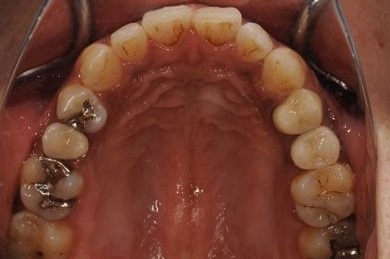

インプラントの症例写真 IMPLANT

| 治療内容 | インプラント2本(ソケットリフト、抜歯即日スピードインプラント)、メタルボンドセラミッククラウン3本(メタルボンドセラミック用土台1本)、ハイブリッドセラミックインレー4本 | ||||||||||||||||||||||||||||||||

| 治療期間 | 10ヶ月 |

治療前